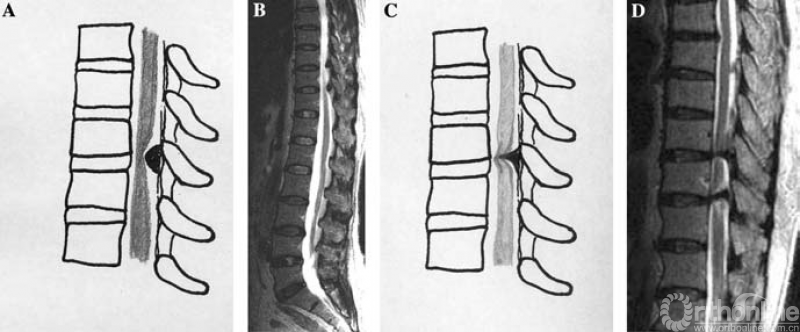

2. MRI分型:按照矢状位MRI分为圆弧形、鸟嘴型。

A.B.圆弧形(Round type);C.D.鸟嘴型(Beak type)